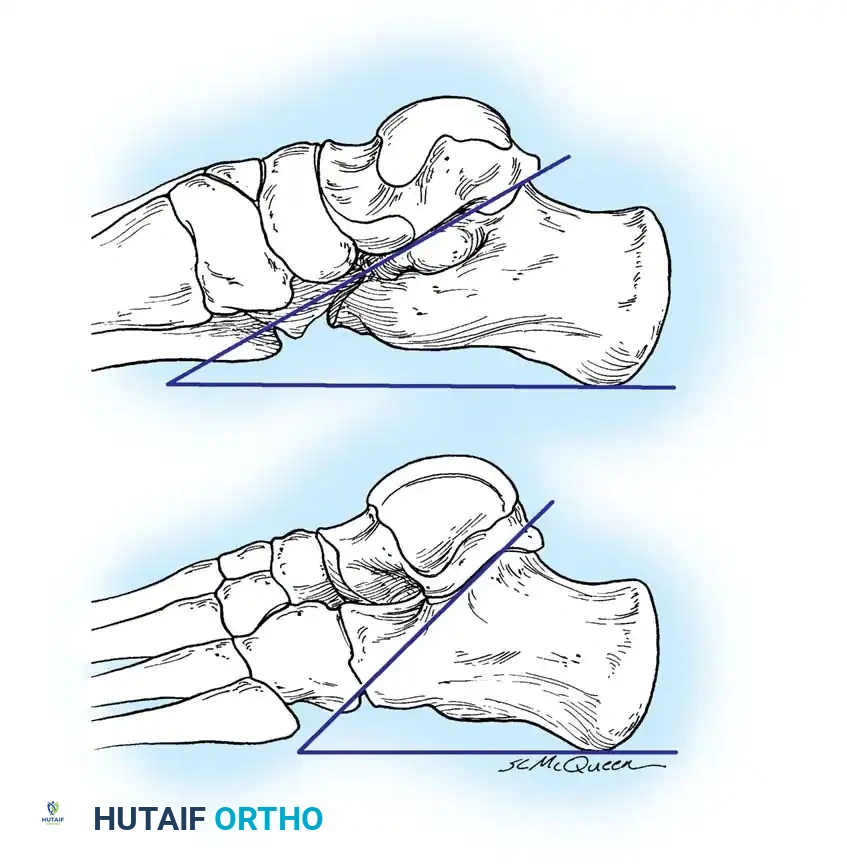

Tarsal Coalition: Pathoanatomy and Genetics

Tarsal coalition is frequently, though somewhat inaccurately, grouped strictly under congenital rigid pes planus. While the anatomical defect is present at birth, symptoms rarely manifest until the cartilaginous bar begins to ossify in late childhood or early adolescence.

Clinical Presentation and Radiographic Evaluation

Ossification Timelines

Because the coalition is initially cartilaginous, the malleability of the peritalar complex prevents significant symptoms in early childhood. As the cartilage ossifies, hindfoot stiffness ensues, and the patient's ability to withstand the microtrauma of vigorous activity declines.

* Calcaneonavicular coalitions typically ossify and become symptomatic between 8 to 12 years of age.

* Talocalcaneal coalitions ossify later, typically between 12 to 16 years of age.

The coalition interface may be bony (synostosis), cartilaginous (synchondrosis), or fibrous (syndesmosis). Paradoxically, incomplete coalitions (cartilaginous or fibrous) are often more symptomatic due to micro-motion at the rigid interface.

Radiographic Imaging

The 45-degree lateral oblique radiograph is the gold standard for diagnosing a calcaneonavicular coalition. The abnormal bar extends from the anterior process of the calcaneus (just lateral to the anterior facet) dorsally and medially to the lateral/dorsolateral extra-articular surface of the navicular. It typically measures 1 to 2 cm in length and 1 to 1.2 cm in width.